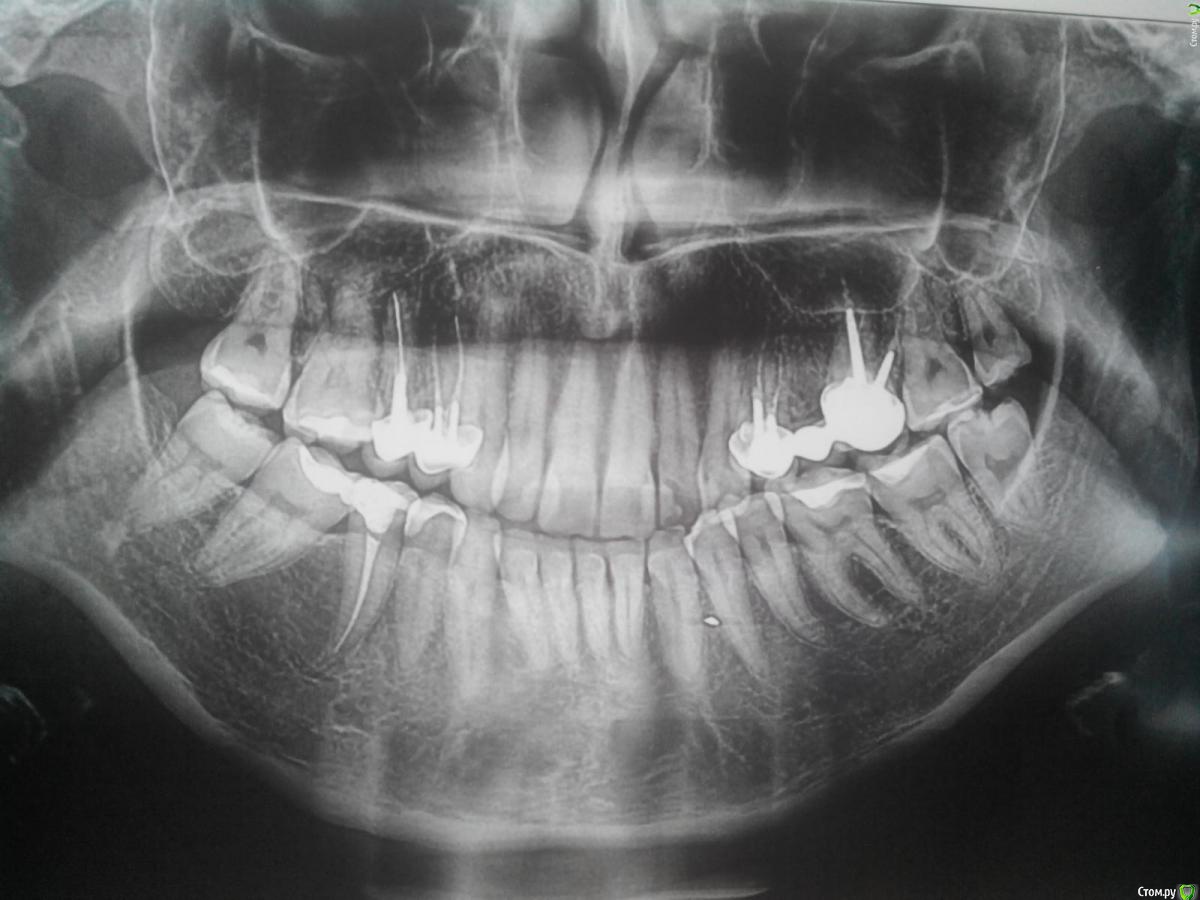

bartons187 Опубликовано 15 апреля, 2015 Автор Поделиться Опубликовано 15 апреля, 2015 Начните с панорамного снимкаСделала снимок Ссылка на комментарий

bartons187 Опубликовано 17 апреля, 2015 Автор Поделиться Опубликовано 17 апреля, 2015 Жду комментариев по снимку. Ссылка на комментарий

Гарриевич Опубликовано 21 апреля, 2015 Поделиться Опубликовано 21 апреля, 2015 Сделайте прицельные снимки в области 15, 14,24,26 зубовНасчет уступов около десны: по снимку они не могут быть видны. Лечение зависит от объема дефектаОдно могу точно посоветовать, ногтем туда не лазайте Ссылка на комментарий

bartons187 Опубликовано 28 апреля, 2015 Автор Поделиться Опубликовано 28 апреля, 2015 Уважаемые врачи. Пока никак не могу сделать прецельный снимок.. Скажите а по остальным зубам в целом какова картина? Нет ли каких- то ещё подозрений? И ещё такой вопрос - есть зуб с пломбой нижний справа 5 как раз под двойной коронкой верхней. Так вот в этом зубе доктору не удавалось сделать примыкание, переделывали один раз и был кусочек пломбы заходивший на зуб снаружи. Спустя время этот кусочек отвалился( пломба на месте, но есть некий уступчик. Что делать? И так же начинает крошиться примыкание ((( зуб лечили года два назад Ссылка на комментарий